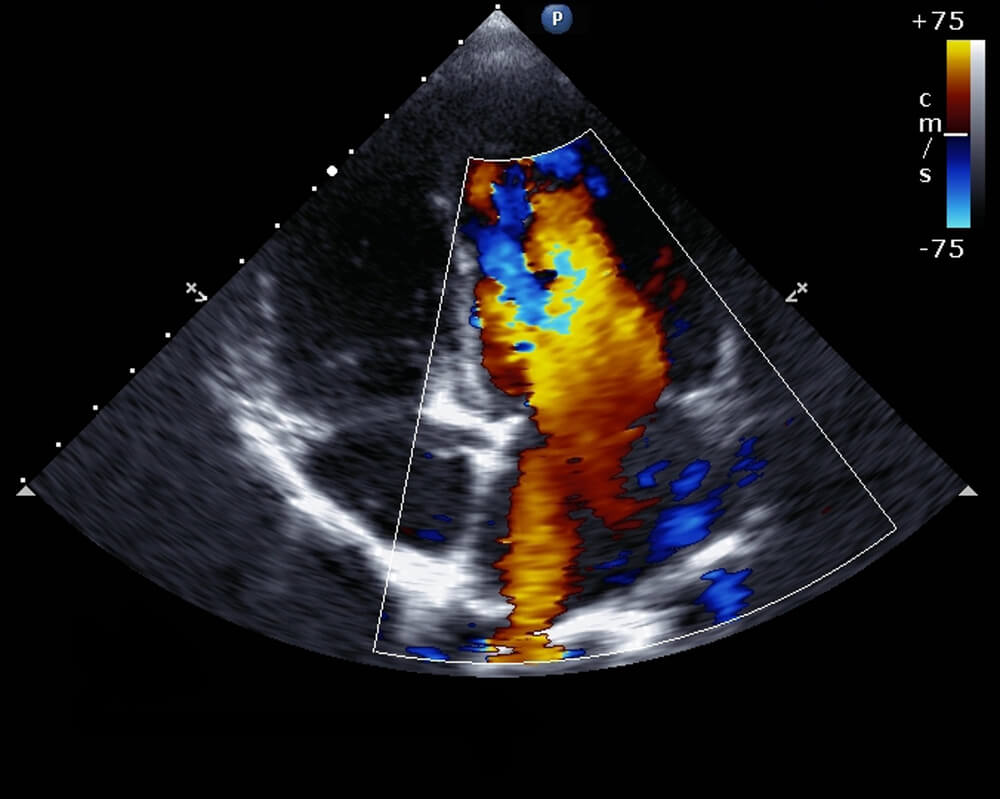

Color Doppler

What is Color Doppler?

Color Doppler is the most advanced ultrasound device that needs to be applied in order to monitor the blood flow in the vessels. Color ultrasound imaging monitors the blood flow in the veins, while at the same time, if there is any narrowing in the veins, it is also useful to investigate the causes. Color imaging, which is often used during pregnancy, can also provide safe imaging in all body parts such as legs, arms, brain, liver.

Color doppler ultrasound, which is a radiological method, is useful for measuring, evaluating and examining the speed of blood in an organ or vessels. This system, where the clearest images can be taken in a short time, is often used to monitor the baby’s health, especially during pregnancy periods, because it is safe.

In contrast to the black and white image of the ultrasound, it provides a color and more detailed examination. While it is used safely in all body parts, it also has all the advantages provided by other ultrasound imaging. By providing real-time imaging, it helps to take the images recommended by specialist physicians, especially at certain times of pregnancy periods. It has a great importance in terms of monitoring the baby’s health and development.